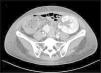

Siete meses después del trasplante, ingresa por un cuadro febril con síntomas respiratorios de un mes de evolución y hematuria macroscópica. Los exámenes complementarios evidencian elevación de reactantes inflamatorios, bicitopenia (anemia y leucopenia) y deterioro de la función del injerto renal. La ecografía renovesical fue normal. Se orientó inicialmente como una infección respiratoria viral con sobreinfección bacteriana añadida, iniciando antibioterapia empírica de amplio espectro y tratamiento profiláctico con trimetroprim/sulfametoxazol dada la linfopenia mantenida; además, se suspendió el MPA, manteniéndose con biterapia inmunosupresora. Ante la ausencia de bacteriuria y negatividad en los estudios microbiológicos iniciales (urinocultivo, hemocultivos, cultivo de esputo, PCR de frotis nasofaríngeo para SARS-CoV-2, VRS e Influenzavirus A y B), ampliamos el estudio con una tomografía computarizada toracoabdominal que evidenció una esplenomegalia y signos sugestivos de nefritis en el injerto renal (fig. 1). Asimismo, ampliamos el estudio microbiológico con frotis respiratorio ampliado y PCR sanguínea para diversos virus con positividad para el adenovirus (440,017 copias/mL), así como su presencia en orina (5,071,409 copias/mL), confirmando la CH secundaria a adenovirus. Dada la persistencia de fiebre y bicitopenia tras la reducción de la inmunosupresión, se planteó el uso de terapia antiviral con cidofovir.